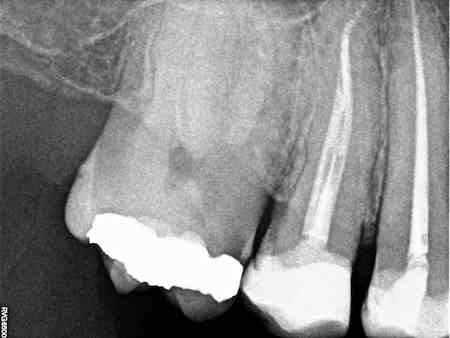

De endodontie of wortelkanaalbehandeling bestaat uit het verwijderen van zenuwen die zich in de wortels van de tanden bevinden. Na het verwijderen zal de tand weer opgevuld worden. Deze behandeling zal u weer een comfortabel gevoel geven.